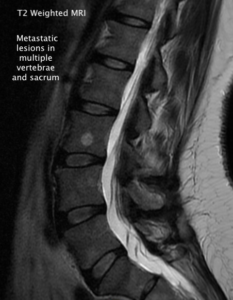

MRI Characteristics of Malignant vs. Benign Lesions (click to open PDF)

1) For the chiropractor to learn the most common causes, locations, and hallmark x-ray findings of compression fractures and spondylolysis.

I. Imaging of Compression Fractures